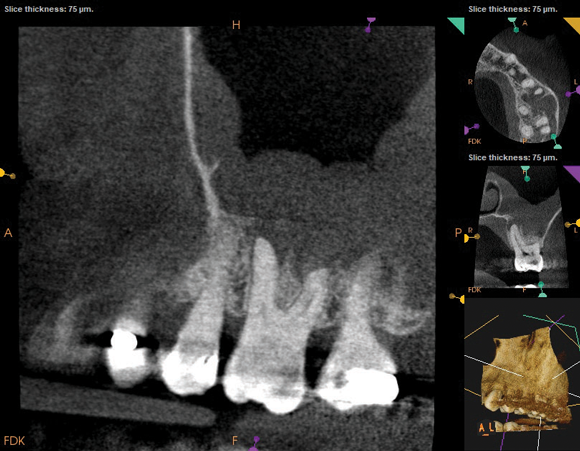

As part of the endodontic evaluation, CBCT imaging showed periapical pathology associated with tooth No. 14 as well as significant MSEO (Figure 7 and Figure 8). Clinical testing confirmed the absence of a cold response but no tenderness to percussion or palpation. A composite buildup was in place, absent evidence of recurrent decay. Soft tissues were unremarkable.

Fig 7 and Fig 8. Preoperative CBCT scans showing evidence of periapical pathology on tooth No. 14 as well as communication with the adjacent maxillary sinus and associated mucositis. Fig 7: Sagittal view, buccal roots No. 14. Fig 8: Sagittal view, palatal root No. 14.

Fig 8. Preoperative CBCT scans showing evidence of periapical pathology on tooth No. 14 as well as communication with the adjacent maxillary sinus and associated mucositis. Fig 7: Sagittal view, buccal roots No. 14. Fig 8: Sagittal view, palatal root No. 14.